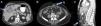

Varón, 76 años, consulta por dolor en hipocondrio derecho y dispepsia en los 3 últimos meses, que se acompaña de acolia, coluria y prurito en los últimos 10 días. El paciente refiere que nota molestias umbilicales que relaciona con herniorrafia previa. Antecedentes médicos: fibrilación auricular y herniorrafia umbilical. Exploración física: dolor en hipocondrio derecho, tumoración pétrea en región umbilical y tinte ictérico. Analítica: GGT: 718UI/l, fosfatasa alcalina: 391UI/L, bilirrubina total: 9,1; CEA: 92,7mg/dl y CA19.9: 206UI/l. Se realiza ecografía y TAC abdominal donde se observa una gran lesión sólida heterogénea de contornos mal definidos, en la región perihiliar, que surge del fondo vesicular y produce dilatación bilateral de la vía biliar intrahepática, las paredes de la vesícula están engrosadas y son hipercaptantes, además presenta colelitiasis múltiple (fig. 1A). Existen múltiples adenopatías en hilio hepático, algunas hasta de 30mm. Implante en región umbilical (fig. 1B y C). Se realiza CTPH y drenaje biliar externo-interno, observando estenosis de la vía biliar por compresión extrínseca. La citología biliar es informada como carcinoma, y la punción de la lesión como adenocarcinoma pobremente diferenciado. Se coloca endoprótesis biliar con normalización del cuadro ictérico, pero desarrolla cuadro de vómitos incoercibles e intolerancia completa a la dieta. Se repite TAC comprobando que existe una marcada dilatación gástrica y esofágica por estenosis en 1.ª porción duodenal por compresión del tumor que ha progresado. Se intenta colocación de prótesis duodenal que no es factible y se decide intervenir para realizar derivación paliativa.